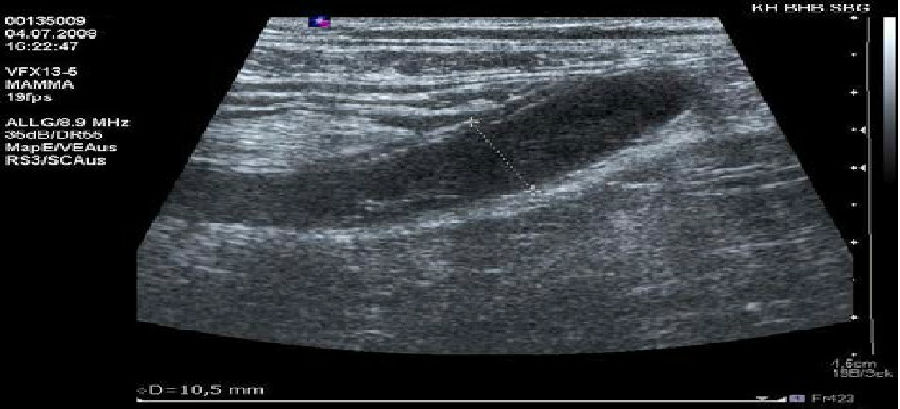

阑尾炎超声声像图超清,阑尾炎超声声像图

阑尾炎超声声像图

阑尾炎超声声像图表现

阑尾炎超声声像图描述